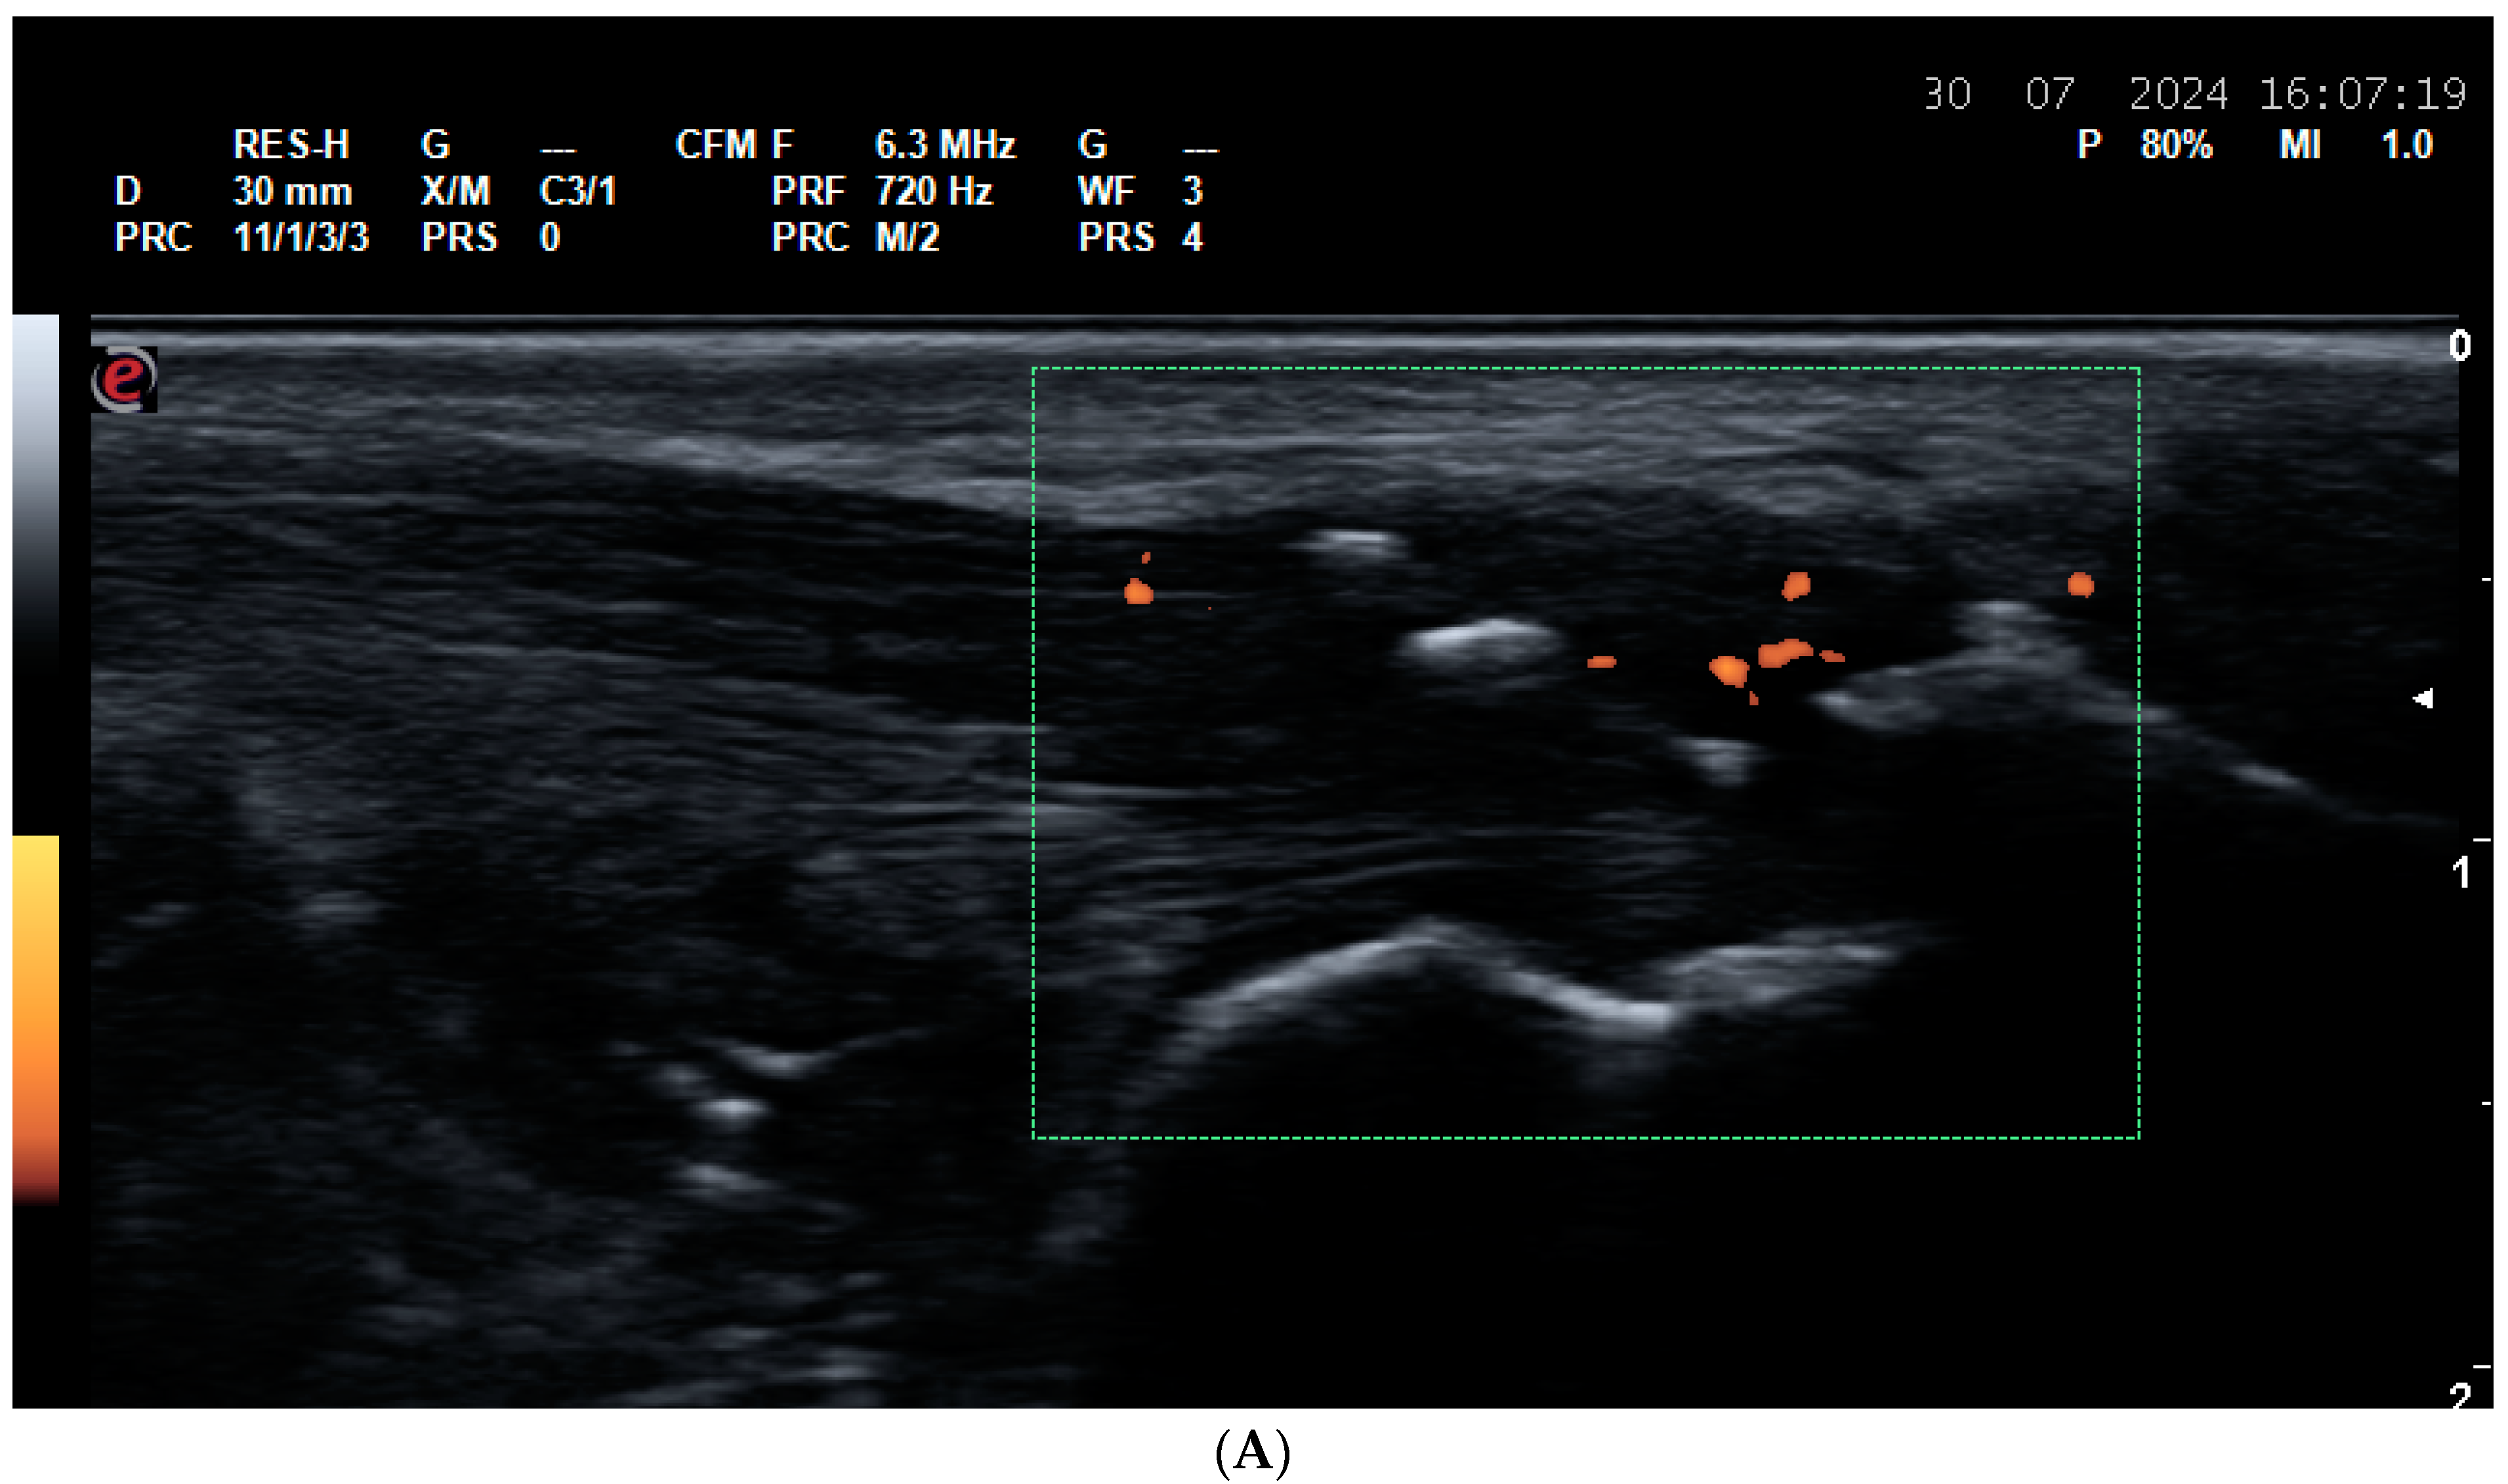

5.2. Vasculitides